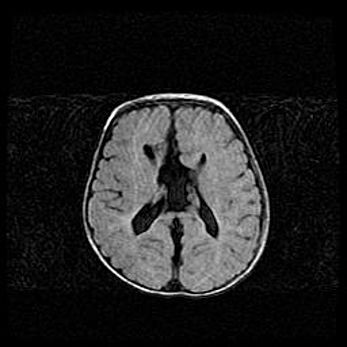

Лейкомаляция с кистозно-глиозной дегенерацией головного мозга.

Возраст: 2 месяца 25 дней

Вес: 6400 г

Окружность головы: 40 см

Срок гестации: 41 неделя

Лейкомаляцию относят к ишемически-гипоксическим повреждениям головного мозга, диагностируемым у новорожденных. При лейкомаляции в головном мозге обнаруживают очаги некроза, возникшие после тяжелой гипоксии и нарушения кровотока. В процессе морфогенеза очаги проходят три стадии: 1) развития некроза, 2) резорбции и 3) формирования глиозного рубца или кисты. Перивентрикулярная лейкомаляция (ПЛ) встречается примерно в 12% случаев среди новорожденных, обычно – у недоношенных детей, причем, частота ее зависит от массы, с которой младенец появился на свет. Наибольшее число малышей страдает лейкомаляцией, если масса при рождении 1500-2500 г.